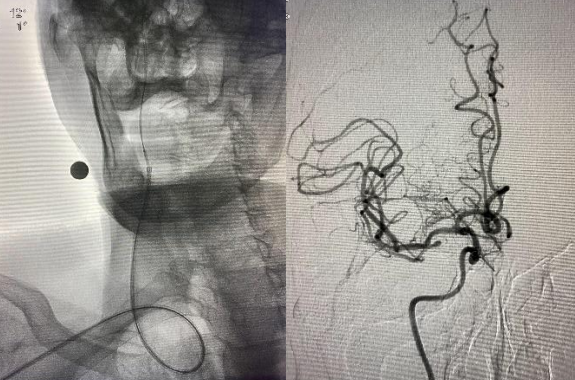

遂果断另辟蹊径,经肱动脉穿刺成功,行腹主动脉造影证实右侧髂总动脉闭塞,左侧髂总动脉极重度狭窄并串珠样改变,故经股动脉入路此路不通。

由远及近,优先开通右侧大脑中动脉恢复颅内血流,再行右侧颈内动脉起始部支架植入血管成形,顺利开通闭塞血管,颅内血流恢复。